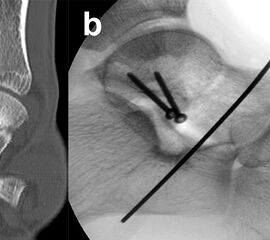

Frakturen des Proc. fibularis tali

Frakturen des Proc. fibularis tali werden im konventionellen Röntgenbild nicht selten übersehen. Sie entstehen häufig nach schweren Distorsionen bzw. im Rahmen subtalarer Luxationen. Eine CT-Kontrolle nach geschlossener Reposition subtalarer Luxationen ist daher obligat (Ab. 15). Der Proc. fibularis tali ist über den anterolateralen Zugang oder schräg verlaufenden Ducroquet-Ollier-Zugang gut zu erreichen. Die subtalare Arthroskopie über anterolaterale und posterolaterale Portale bietet wie bei intraartikulären Kalkaneusfrakturen die Möglichkeit der exakten Kontrolle der geschlossenen Reposition bei einfachen Frakturformen 35. Nach anatomischer Reposition und temporärer Fixierung mittels 1,0 Kirschnerdraht erfolgt die Osteosynthese mittels Kleinfragmentschrauben (2,7 bzw. 3,5 mm), die unterhalb der Knorpel- Knochengrenze eingebracht werden und für eine ausreichende Stabilität sorgen (Abb. 16). Kleinere, nicht anatomisch refixierbare Fragmente, oder Fragmente mit starker Knorpelkontusion werden vorzugsweise exzidiert (Abb. 17). Gleiches gilt für Frakturen des Proc. posterior tali zur Vermeidung einer posttraumatischen Arthrose 23736.